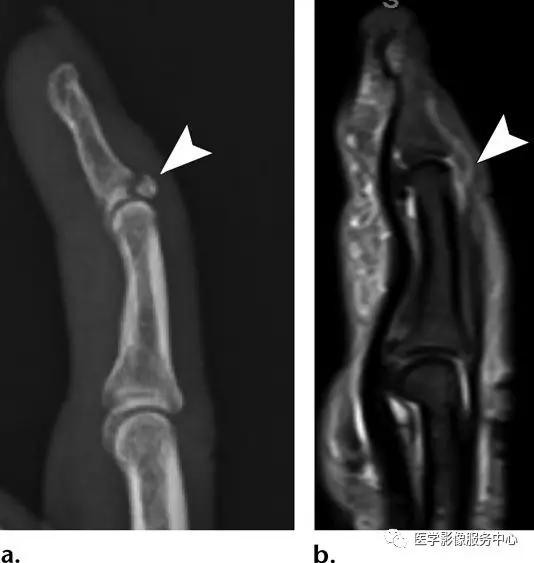

Jersey指:

远端指骨的掌侧基底部向近端移位的骨片(白色箭头),主要的远端指骨骨片向背侧移位。远端指骨干骺端的横断性骨折。这些表现符合指深屈肌腱的骨性撕脱骨折。

指深屈肌腱的撕脱损伤:

食指及中指创伤性截肢,食指指深屈肌腱(白色箭头)连接于远节指骨的掌侧基底面(黑色箭头)。